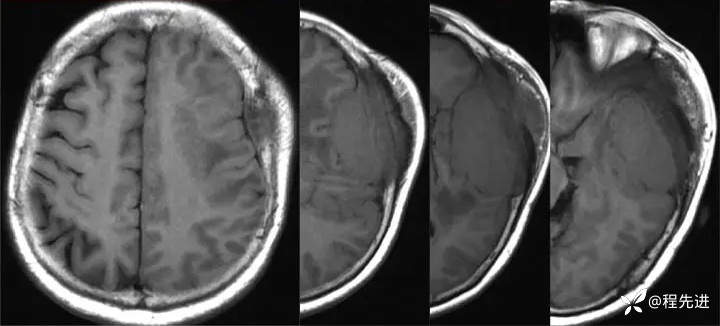

【患者信息】:女,58岁

【现病史及既往史】:发现头皮肿块,进行性增大2年余

影像检查: